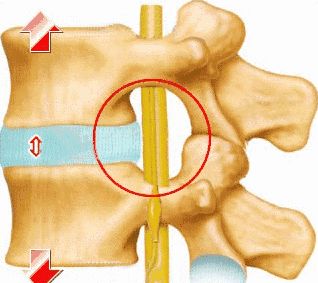

其中,腰椎间盘突出症是由于腰椎间盘退变、纤维环破裂、髓核突出而刺激或压迫脊神经根、马尾神经所表现的一种临床综合征。

其典型症状是从下腰部向臀部、大腿后方、小腿外侧直到足部的放射痛,特别是在咳嗽、打喷嚏等腹压突然增高的情况下,疼痛会加剧。

“腰椎间盘突出症已成为困扰现代人的常见病,目前的治疗方式存在局限性,并不能解决患者病痛。”唐海说,传统的中医治疗主要是牵引,朝上下两个方向牵拉,撑开椎间隙,牵拉后纵韧带,这样使椎间盘被回纳,不再压迫脊髓。

BacFuse系统是一种后路、非椎弓根固定系统,适用于颈椎之外的单阶段椎体疾病,通过植入BacFuse棘突间融合器,撑开棘突间隙,一方面有利于突出的椎间盘回缩到原始位置,修复椎间盘。另一方面通过牵拉后纵韧带、黄韧带,增加椎管面积。

这种手术不动大的腰椎结构和椎间盘,只破坏棘间韧带,放入一个撑开器,在两个相邻棘突间“叠瓦状”固定,以增大棘突间的应力作用,让重力通过棘突间内置物向下传导,减少受损椎间盘的压力,从而让突出的椎间盘自己慢慢复位。

所以,这种手术也被称为“脊柱内牵引”,避开了传统体外牵引的弊端,同时还能与骨移植材料一起使用。